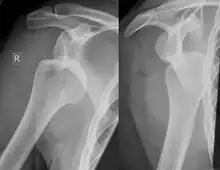

Diagnosis can be suspected by history and physical examination which is usually followed by imaging. Because of the mechanism of injury, apprehension of anterior dislocation is common with provocative maneuvers. Hill–Sachs lesions have been classified as "engaging" or "non-engaging", with engaging lesions defined by the ability of the glenoid to sublux into the humeral head defect during abduction and external rotation. Engaging dislocations have a higher risk of recurrent anterior dislocation, and their presence can help guide surgical management.[2] Imaging diagnosis conventionally begins with plain film radiography. Generally, anteroposterior (AP) radiographs of the shoulder with the arm in internal rotation offer the best yield while axillary views and AP radiographs with external rotation tend to obscure the defect. However, pain and tenderness in the injured joint make appropriate positioning difficult and in a recent study of plain film x-ray for Hill–Sachs lesions, the sensitivity was only about 20%. i.e. the finding was not visible on plain film x-ray about 80% of the time.[3]

The incidence of Hill–Sachs lesion is not known with certainty. It has been reported to be present in 40% to 90% of patients presenting with anterior shoulder instability, that is subluxation or dislocation.[8][9] In those who have recurrent events, it may be as high as 100%.[10] Its presence is a specific sign of dislocation and can thus be used as an indicator that dislocation has occurred even if the joint has regained its normal alignment. Large, engaging Hill-Sachs fractures can contribute to shoulder instability and will often cause painful clicking, catching, or popping. The average depth of Hill–Sachs lesion has been reported as 4.1 mm.[11]